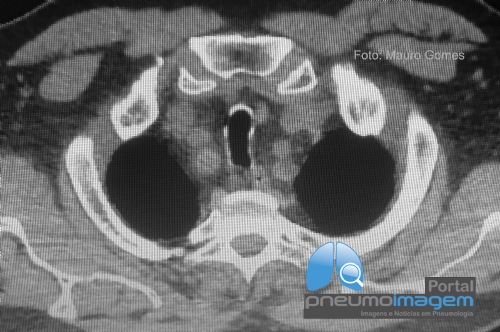

CASO CLÍNICO #57

Paciente masculino de 64 anos, tabagista com dispneia, tosse persistente e a seguinte imagem radiológica. Qual o nome desse sinal e o provável diagnóstico? Deixe seus comentários abaixo!

A 64-year-old male smoker with dyspnea, persistent cough and the following radiological image. What is the name of this sign and the likely diagnosis? Write your comments below!